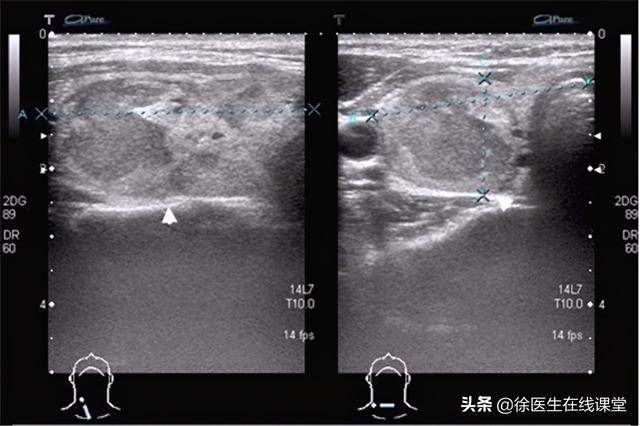

甲状腺结节的类型较多,比如甲状腺囊肿,它占甲状腺结节的15%~20%,可以说是大多数患者最容易患上的甲状腺结节之一,除此之外是胶质结节,不过这种结节单发性较少,女性的发病率高,在女性年轻以及怀孕的时候,很容易患上这种疾病,有没有哪种类型是单发性甲状腺结节癌变率较高的呢?